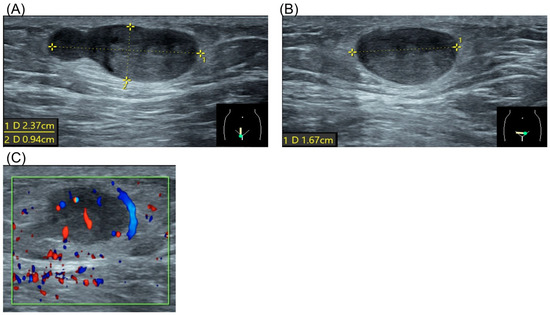

2. Case Report